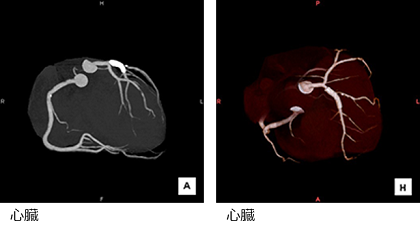

CT画像(例)

大血管